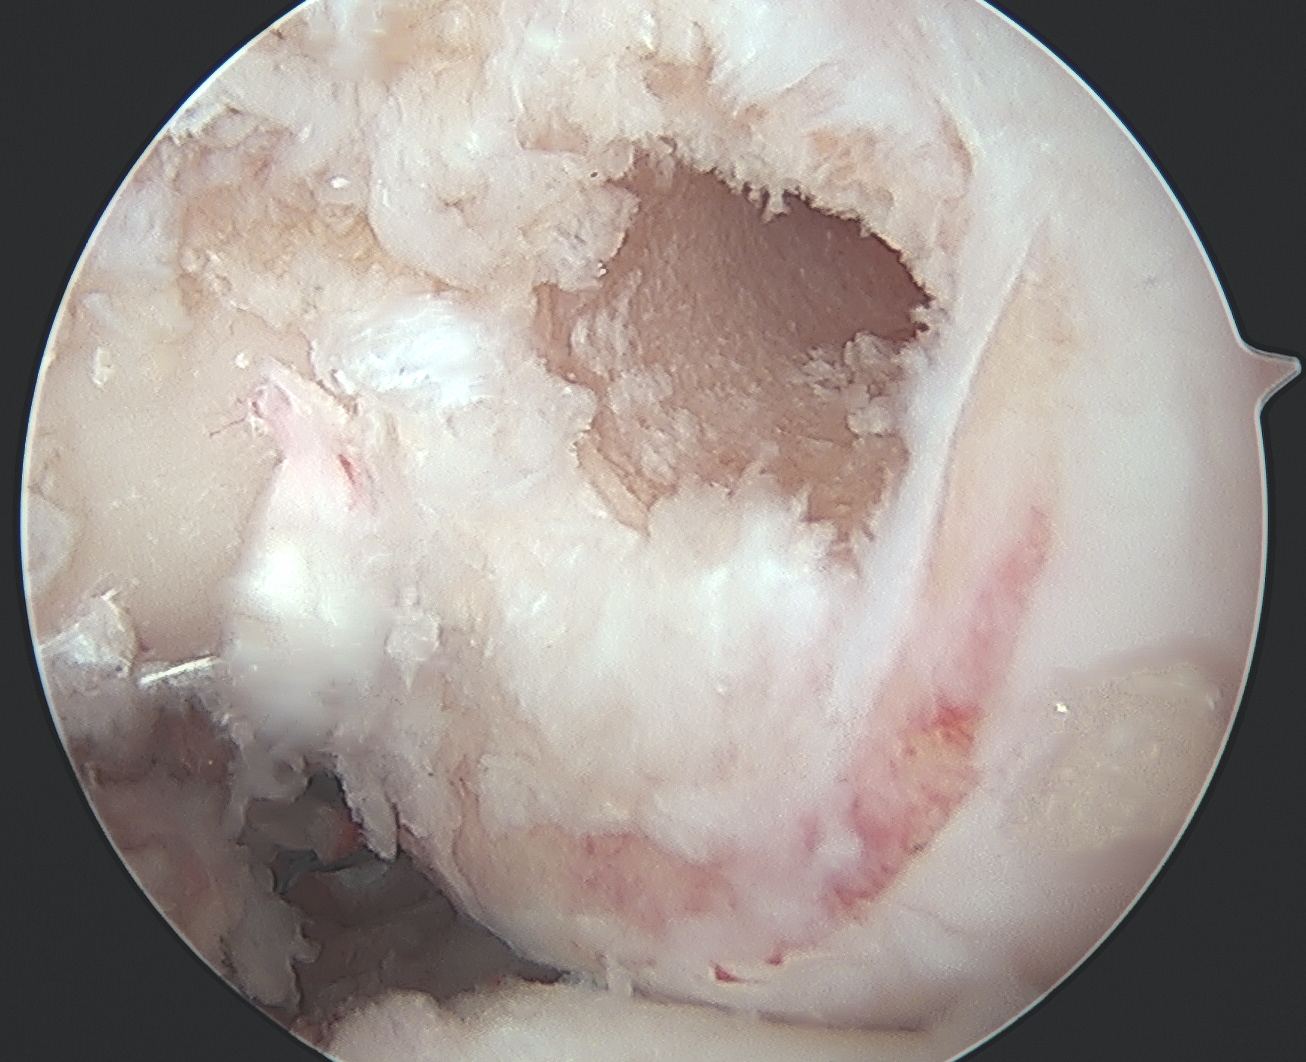

Debridement of notch

Place posteromedial cannula

- most common mistake is placing cannula too anterior / inferior

- need to be able to instrument PCL origin

- also allows direct visualisation with camera

Assess / treat meniscus